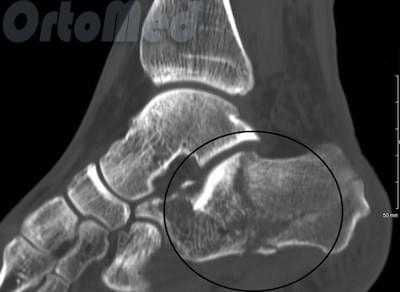

Пациент М. 1980 г.р., травму получил при падении на стопы с высоты 1,5 метра. Лечился по месту жительства (в травмпункте районной больницы) консервативно в гипсовой повязке в течение 14 дней. Консультирован в травматологическом отделении ФГБУ «УНИИТО им. В.Д. Чаклина» Минздрава РФ, предложено оперативное лечение. При поступлении кожные покровы стопы чистые, без признаков воспаления и сдавления тканей. Стопа отечна, уплощена. На рис. 1 представлены рентгенограммы пациента. Прооперирован через 2 недели после травмы. Операция состоит из двух этапов. Первый этап заключается в наложении дистракционного аппарата. Проводятся две спицы 1,8 мм во фронтальной плоскости: первая через нижнюю треть диафиза большеберцовой кости, вторая через бугор пяточной кости (рис. 2). Спицы фиксируются в дистракционном аппарате, выполненном из двух полуколец, соединенных между собой двумя телескопическими тягами. Особое расположение полуколец, фиксация спиц на концах полуколец, крепление кронштейнов для телескопических тяг обеспечивает тракцию пяточной кости в необходимом направлении с использованием минимального количества спиц и внешних опор при сохранении необходимого поля обзора для проведения рентгенологического и визуального контроля репозиции и фиксации. Второй этап - закрытая элевация импрессированной суставной поверхности и окончательная репозиция пяточной кости. Через разрез длиной до 1 см по латеральному краю ахиллова сухожилия (рис. 3) в месте его прикрепления к пяточной кости под соответствующий фрагмент подводится элеватор (рис. 4), манипуляцией которым устраняется смещение и выполняется провизорная фиксация спицами 1,5 мм (рис. 5). При сагиттальном раскалывании суставной фасетки целесообразно проведение одного-двух винтов субхондрально (рис. 6). Стержень вводится с дорзальной поверхности пяточной кости по ее оси через разрез до 2 см по предварительно сформированному остеотомом каналу (рис. 7, 8). Далее через проколы кожи с помощью кондуктора (рис. 9) выполняется запирание винтами с латеральной поверхности, внешнее устройство демонтируется. Достигнуто удовлетворительное стояние отломков (рис. 10).

Рис. 1. На рентгенограмме левой стопы в прямой и боковой проекциях определяется оскольчатый внутрисуставной перелом левой пяточной кости